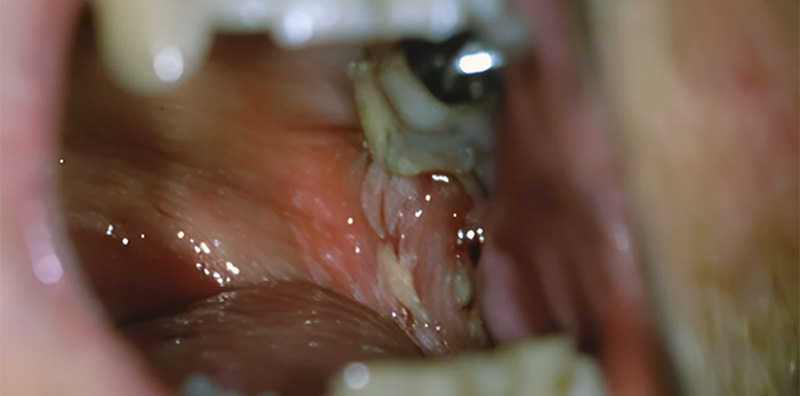

Cancer de la commisure inter-maxillaire : région rétro-molaire

Les cancers de la commissure inter-maxillaire représente 25 % des cancers de la cavité buccale.

Fig. 08 : cancer de la gencive inter-incisif.